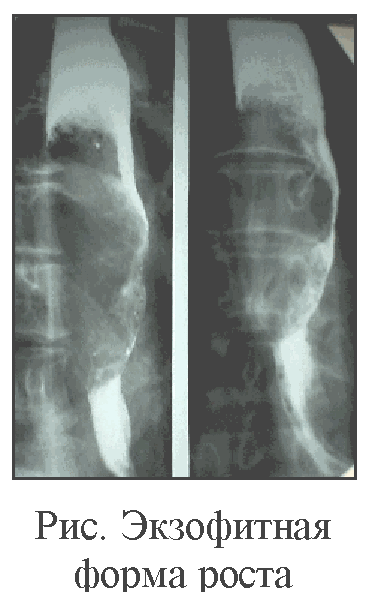

Рис. 59. Экзофитный рак пищевода при тугом наполнении контрастным веществом и в фазе пневморельефа. Складки слизистой оболочки в области опухоли разрушены, контуры пищевода неровные.

По клинико-рентгенологическим признакам можно выделить эндофитную, или инфильтративную, экзофитную, или полипозную, и смешанную формы рака. Экзофитная опухоль может изъязвляться и приобретать форму смешанной блюдцеобразной карциномы.

Экзофитный (полипозный) рак растет преимущественно в просвет пищевода, образуя в нем при заполнении контрастом дефект наполнения с неправильными, полициклическими очертаниями. При циркулярном расположении экзофитной опухоли пищевод на определенном протяжении становится суженным, контуры сужения неровные, ригидные. Переход от суженного участка к нормальному контуру часто обрывистый, ступенчатый. В зоне опухоли складки слизистой оболочки разрушены, внутренняя поверхность пищевода образована рельефом опухолевых масс в виде множественных узлов неправильной формы. Изъязвления поверхности опухоли образуют стойкие депо контрастного вещества с неровными контурами (рис. 61).